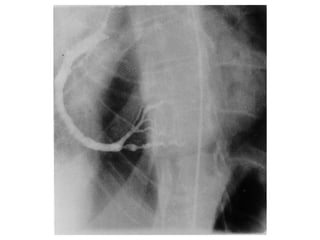

Review of LHC from 2006 STEMI

Review of LHCfrom 2006 STEMI